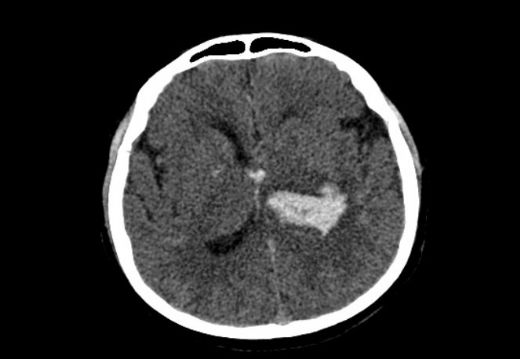

Hipertansiyon, yani yüksek tansiyon, günümüzde birçok insanı etkileyen ciddi bir sağlık sorunudur. Uzun süreli yüksek tansiyon, damarlarda ve özellikle beyin damarlarında hasara yol açabilir. Bu hasar, beyin kanaması gibi ciddi sağlık problemlerine neden olabilir. Bu makalede, hipertansiyona bağlı beyin kanamasının belirtileri ve tedavi yöntemleri detaylı bir şekilde ele alınacaktır. Hipertansiyonun Beyin Üzerindeki Etkileri Hipertansiyon, beyin damarlarının yapısını etkileyerek kanama riskini artırır. Yüksek kan basıncı, damarların duvarlarını zayıflatabilir ve bu durum, anevrizma (damar genişlemesi) veya damar yırtılması gibi durumlara yol açabilir. Hipertansiyonun beyin üzerindeki etkileri arasında:

Beyin Kanamasının Belirtileri Hipertansiyona bağlı beyin kanamasının belirtileri, genellikle ani ve şiddetli bir şekilde ortaya çıkar. Bu belirtiler arasında:

Bu belirtiler ortaya çıktığında, acil tıbbi müdahale gereklidir. Tedavi Yöntemleri Hipertansiyona bağlı beyin kanamasının tedavisi, kanamanın yerine, büyüklüğüne ve hastanın genel sağlık durumuna bağlı olarak değişiklik göstermektedir. Genel olarak tedavi yöntemleri:

Sonuç Hipertansiyon, beyin kanaması riskini artıran önemli bir faktördür. Belirtilerin ani bir şekilde ortaya çıkması, acil müdahale gerektiren durumlardır. Tedavi süreci, hastanın durumuna göre değişiklik göstermekle birlikte, önleme yöntemlerinin uygulanması hipertansiyonun kontrol altına alınmasında büyük önem taşımaktadır. Sağlıklı yaşam tarzı değişiklikleri ve düzenli doktor kontrolleri ile beyin kanaması riski önemli ölçüde azaltılabilir. |

Endişelenmen oldukça anlaşılır. Hipertansiyona bağlı beyin kanaması ciddi bir durumdur ve belirtilerini erken fark etmek önemlidir. Beyin kanamasının belirtileri arasında aniden başlayan şiddetli baş ağrısı, bilinç kaybı, konuşma güçlüğü, görme sorunları, kol veya bacakta ani güçsüzlük veya hissizlik, denge kaybı ve koordinasyon problemleri yer alır. Eğer bu belirtilerden herhangi birini fark edersen ya da şüphelenirsen, vakit kaybetmeden doktora başvurmalısın. Erken müdahale, tedavi sürecinde büyük fark yaratabilir. Sağlıklı günler dilerim.